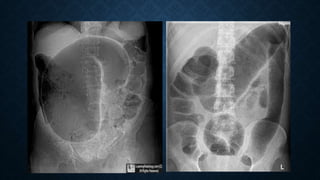

B. Abdominal X Ray Studies:

• Multiple air fluid level or 3 , 6 , 9 rules or string of Pearl sign to

identify intestinal obstruction.

X RAY CONTD.

Pneumoperitoneum: usually by suggests a perforated viscous

1 ml air in peritoneum produce pneumoperitoneum in upright CXR

5-10 ml air in peritoneum produce pneumoperitoneum in lateral decubitus position

(after 10 minutes)

Pneumoperitoneum is usually not found in Burst appendix.